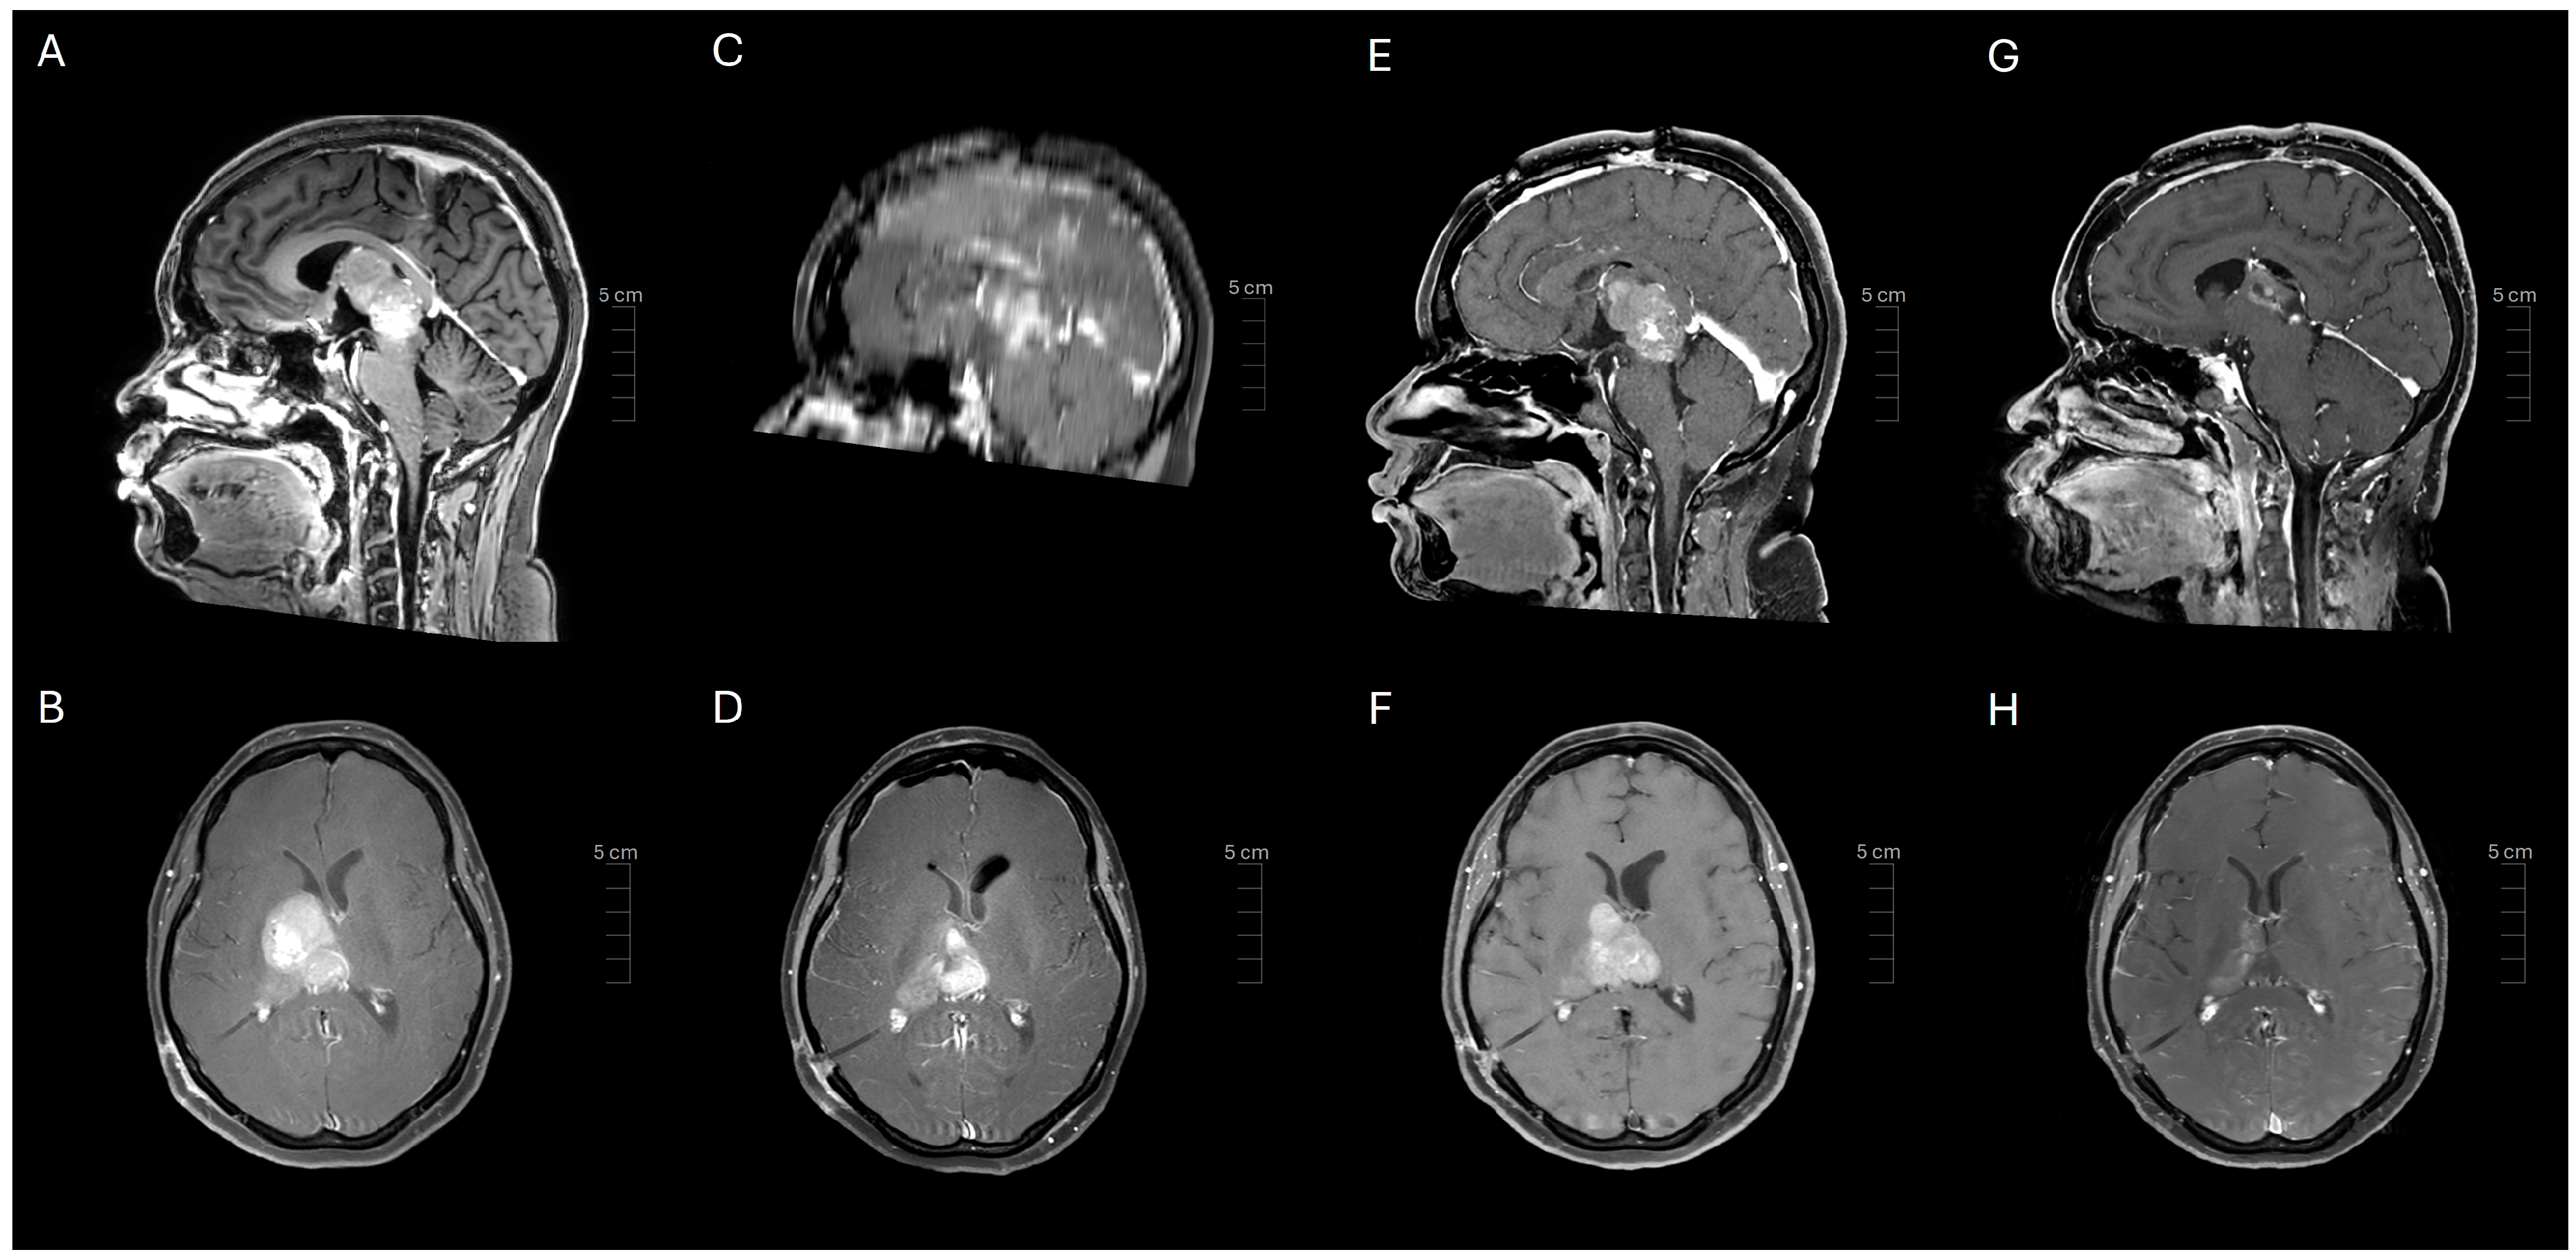

2. Case Presentation